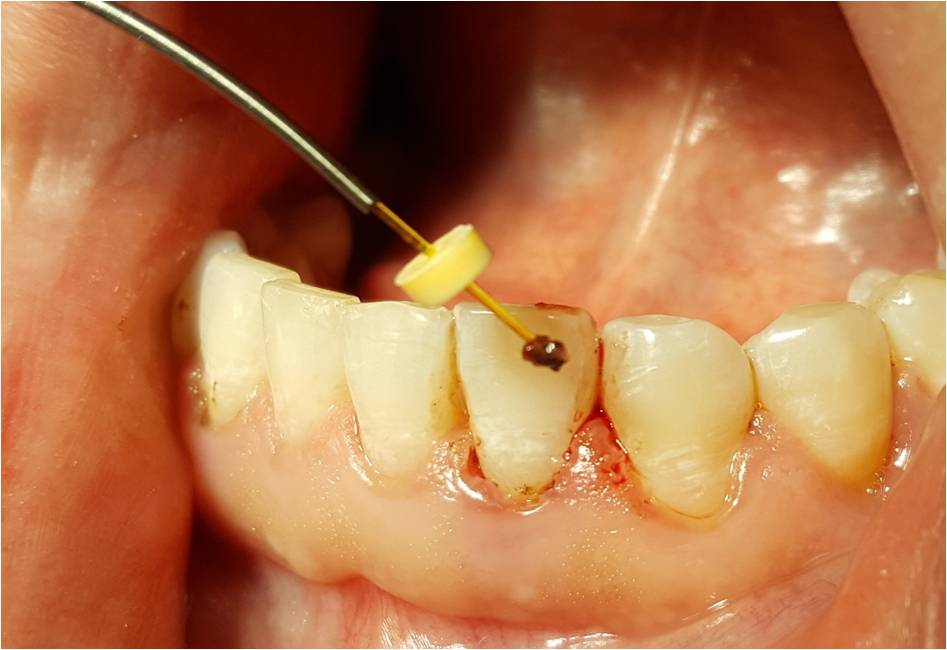

- Opis przypadku: 37-letni pacjent zgłosił się do Poradni Stomatologii Zachowawczej i Chorób Przyzębia w Zabrzu z powodu krwawienia dziąseł podczas szczotkowania oraz nieprzyjemnego zapachu z ust